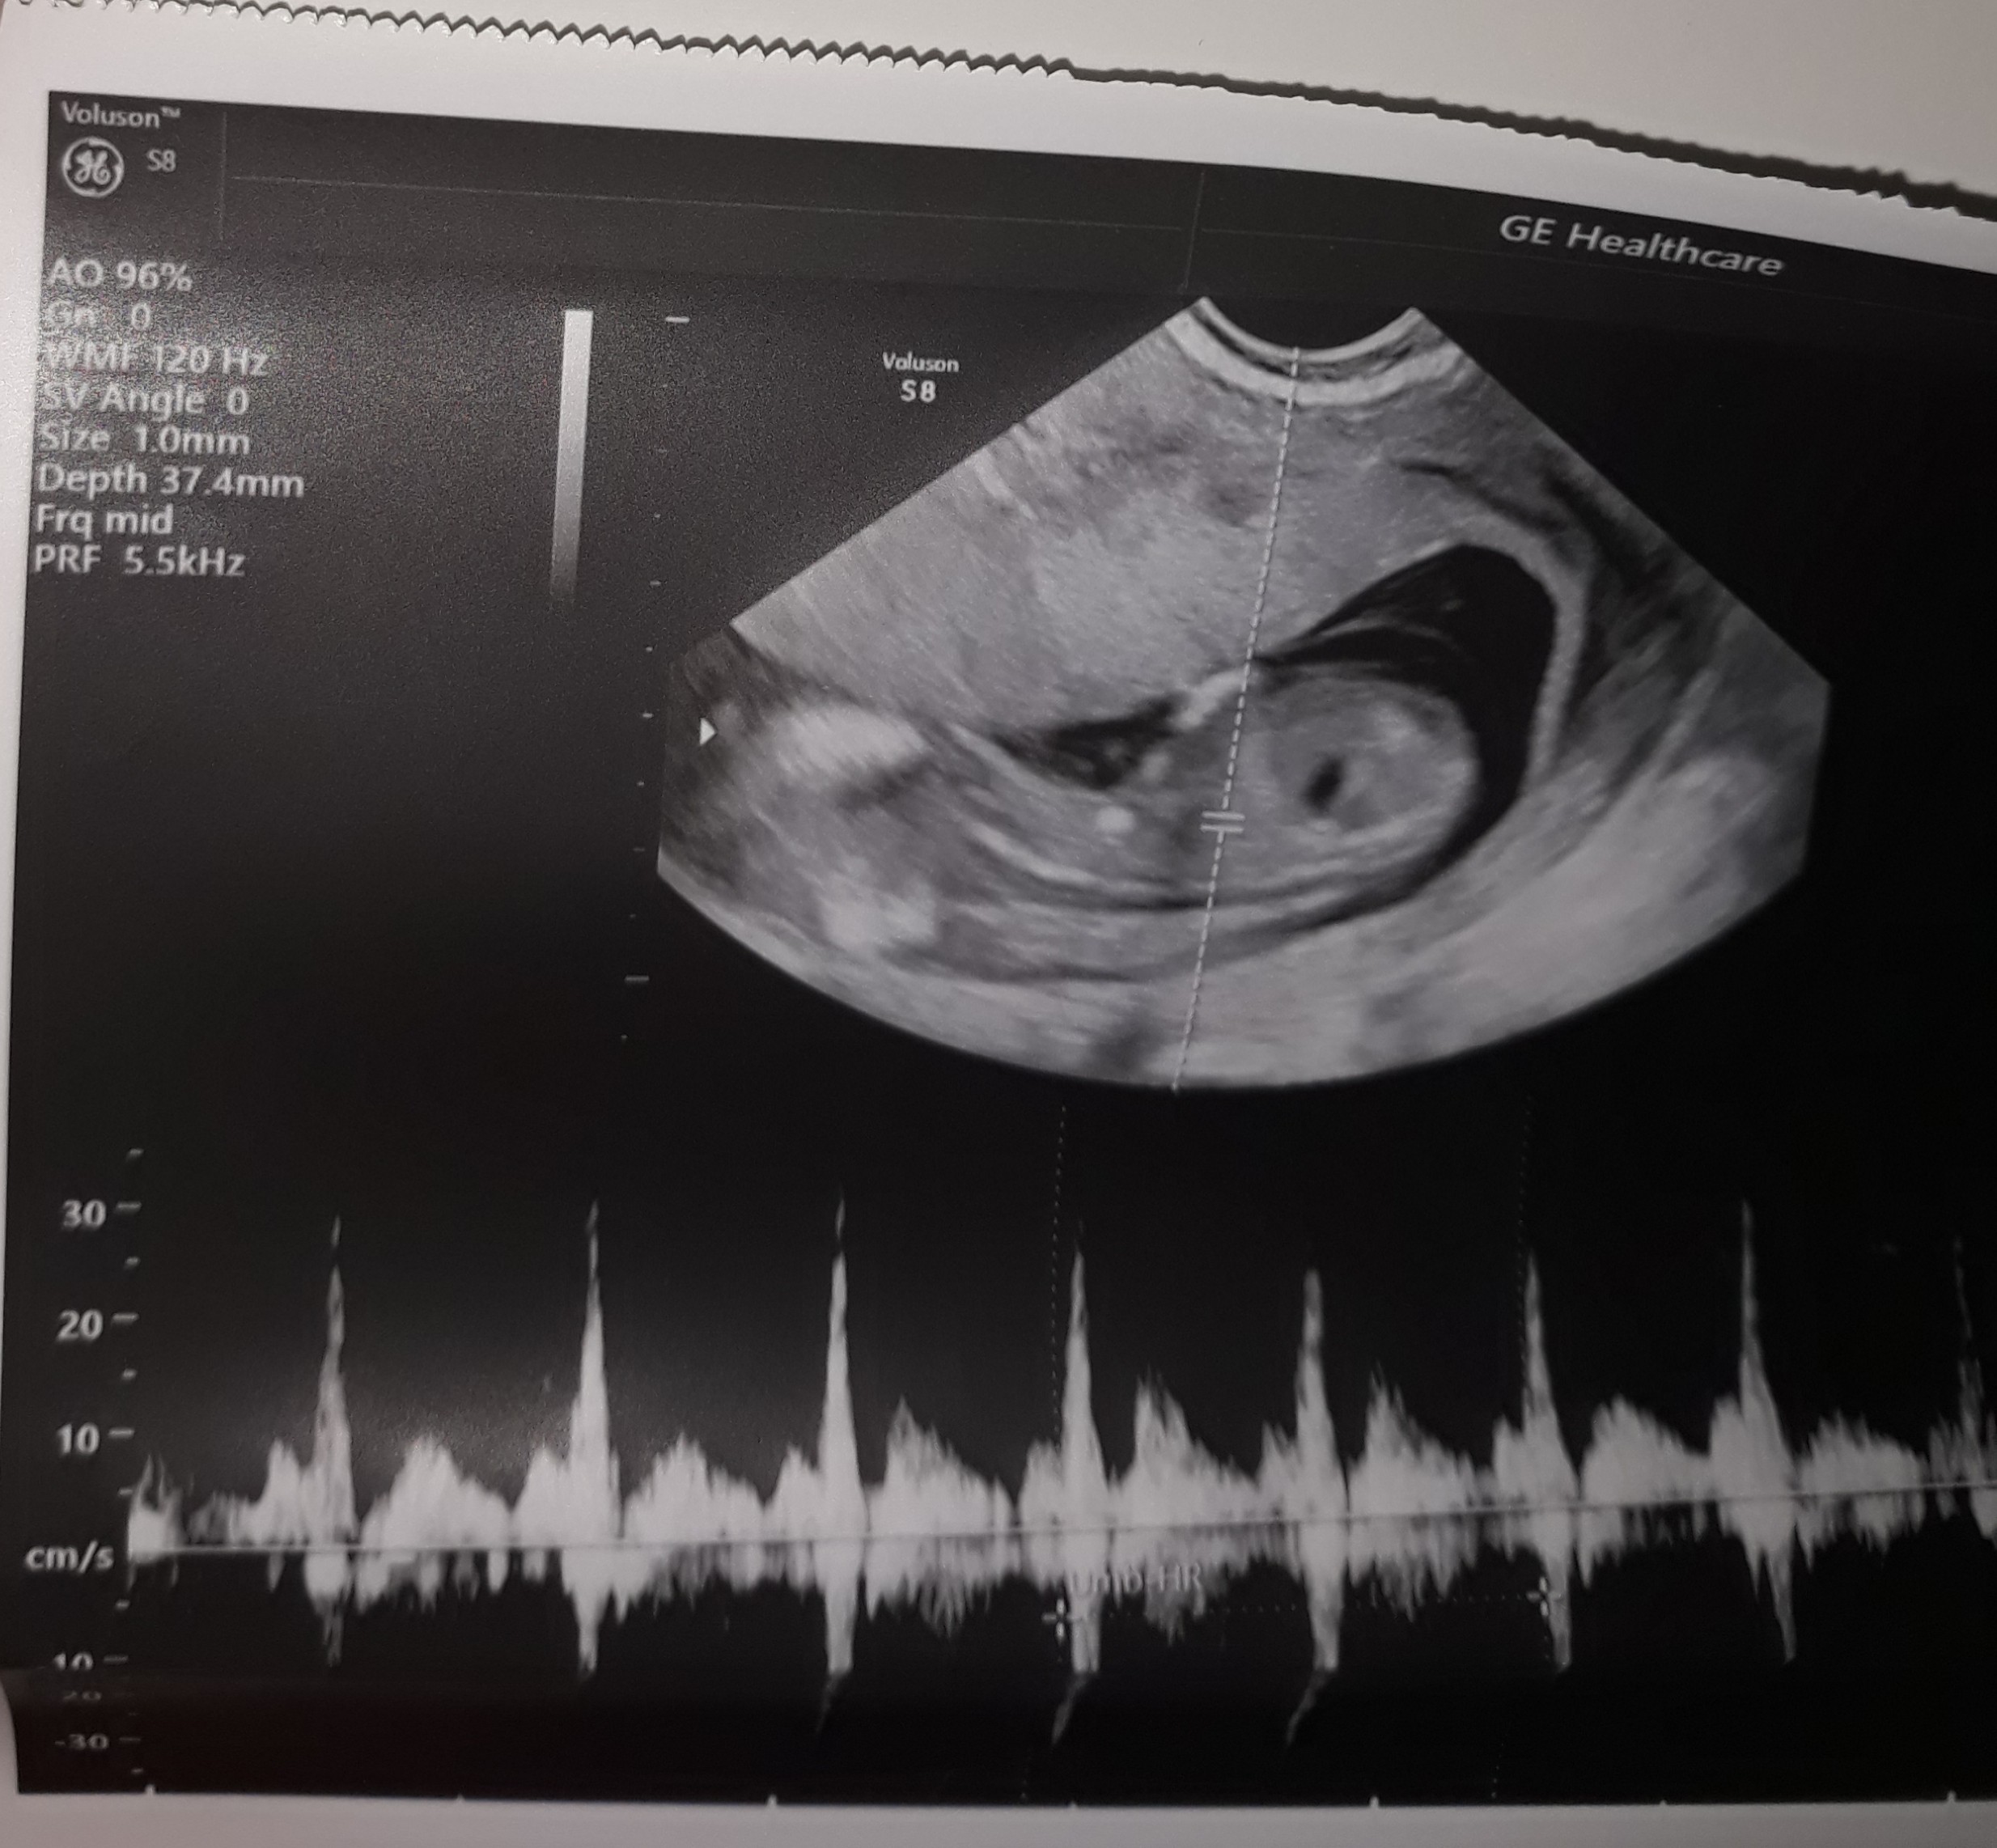

Witam , wiem , że to może głupie pytanie , ale to moja 1 ciąża i się wszystkim przejmuję. Dlaczego te usg jest takie dziwne , zamazane ? Wogóle nie widać kształtów dziecka. Czy któras też tak miała?

Tylko takie zdjęcie masz ? Wygląda trochę jakby była próba łapania przezierności, ale dziwnie nie bokiem tylko tyłem, to drugie chyba jest z pomiarem crl i wygląda na pierwszy rzut oka lepiej, ale też bez szału. Dzidzuś się mocno ruszał? Słabe to zdjęcie, a to ważne usg, masz opis taki porządny ze wszystkimi pomiarami itd.? Jak nie to może powtórz u kogoś z lepszym sprzętem...

To jest kolejne zdjecie z serduszkiem albo jakimiś przepływami, nie masz żadnego papierowego opisu do zdjęć? To było u Twojego prowadzącego czy gdzieś zewnetrznie robiłaś samo usg? Robiłaś test pappa? Czasem jest tak że opis dają dopiero po wynikach skorygowanych z pappa, ale to byś chyba wiedziala?